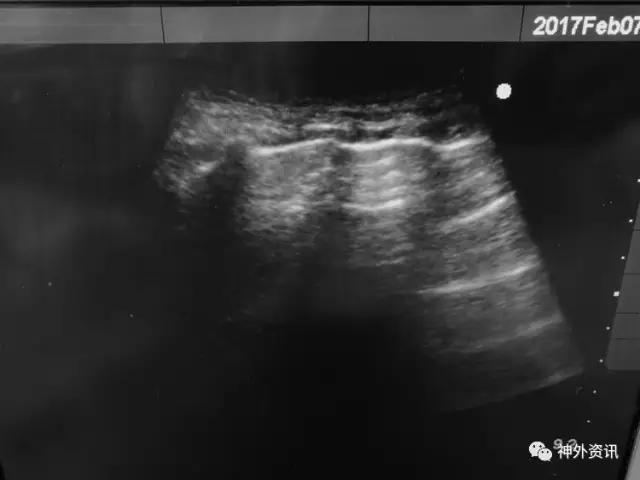

胸部CT及超声显示双肺底存在肺不张:

前胸超声:

肺底超声: